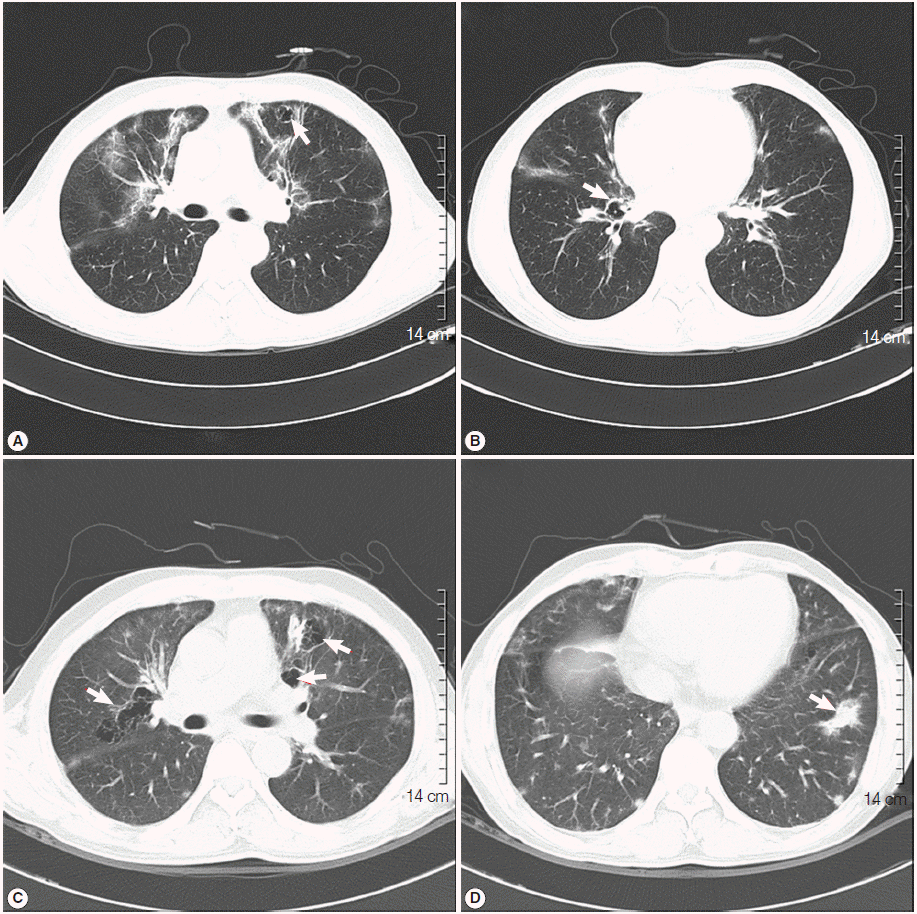

Bronchoscopy was performed, but no endobronchial lesions were observed. Bronchoalveolar lavage (BAL) was performed in the right middle lobe. Cell counts in BAL revealed a lymphocyte-dominant leukocytosis (white cells 342/μl, neutrophils 9%, lymphocytes 37%, eosinophils 5%, and macrophages 49%). Further analysis of lymphocyte subsets showed a predominance of cytotoxic T cells (cytotoxic T cells 98.3%, T helper cells 1.7%, natural killer cells 3%, and B cells 0.1%). Cytologic studies, acid-fast bacillus stain, and PCR for tuberculosis and non-tuberculotic mycobacteria in the BAL fluid exhibited negative results. A tuberculin skin test and interferon-γ release assay (Quantiferon®; Carnegie, Victoria, Australia) were also negative. A video-assisted wedge resection of the left upper lobe was performed. Upon histological examination, hematoxylin and eosin (H&E) staining revealed eosinophilic frothy exudates in alveolar spaces accompanied by mild interstitial inflammation, and Grocott-Gomori’s methenamine silver (GMS) stains, performed during the histological examination, revealed many cystic- and trophic-form organisms (arrows) in the alveolar exudate, consistent with P. jirovecii infection (Fig. 3). Trimethoprim-sulfamethoxazole (TMP-SMX) was administered orally (2 double strength TMP-SMX tablets every 8 hr) [11]. The patient’s fever subsided within 3 days (from 38.5˚C to 37.0˚C), and the streaky and fibrotic lesions observed in both lungs on the chest X-ray were also markedly improved (Fig. 1B) after 12 days of TMP-SMX administration, which enabled the patient to be discharged.

TMP-SMX treatment continued to be administrated for additional 17 days following the patient’s discharge from the hospital. However, the patient complained of cough again, and a follow-up chest X-ray showed aggravation of the streaky and fibrotic lesions in both lungs (Fig. 1C). The patient was readmitted to the hospital, and chest CT was rechecked. A follow-up chest CT revealed an aggravation of multifocal peribronchial ground-glass opacity and septated cystic lesions in both upper lungs, and a newly appeared consolidation in the left lower lobe (Fig. 2C, D). P. jirovecii was clinically suspected to be resistant to TMP-SMX, and molecular studies carried out using PCR with primers Dp15 (5´-TCTGAATTTTATAAAGCGCCTACAC-3´) and Dp800 (5´-ATTTCATAAACATCATGAACCCG-3´) demonstrated mutations at codons 55 and 57 of the dihydropteroate synthase (DHPS) gene as a previous report [12].

Primaquine (4 mg/kg/day intravenous once daily) and clindamycin (600 mg intravenous every 8 hr) were administrated for 3 weeks in place of the TMP-SMX. Consequently, the cough was resolved, and a follow-up chest X-ray showed improvement of the streaky and fibrotic lesions in both lungs (Fig. 1D). We strongly suspected that HIV infection was an underlying condition, and rechecked the HIV immunoassay, which was determined to be positive. Further evaluation of HIV infection was performed; the titer of HCV RNA was determined to be 110,000 copies/ml, and the number of T helper cells in the peripheral blood was only 3/μl. Antiviral treatment regimen targeting the HIV was initiated, including lopinavir (800 mg/day), ritonavir (200 mg/day), lamivudine (300 mg/day), and zidovudine (600 mg/day), and the patient was discharged.

Fig. 1.

Initial chest X-ray and follow-up chest X-rays after the initiation of treatment for Pneumocystis jirovecii pneumonia (PCP). (A) Initial chest X-ray showed streaky and fibrotic lesions in both lungs. (B) In the follow-up chest X-ray performed 12 days after the initiation of TMP-SMX treatment, the lesions were markedly improved. (C) In a follow-up chest X-ray carried out 29 days after the initiation of TMP-SMX treatment, streaky and fibrotic lesions in both lungs were aggravated. (D) In the follow-up chest X-rays, performed 21 days after changing the anti-PCP therapy from TMP-SMX to primaquine-clindamycin, the lesions were improved again.

Fig. 1. Initial chest X-ray and follow-up chest X-rays after the initiation of treatment for Pneumocystis jirovecii pneumonia (PCP). (A) Initial chest X-ray showed streaky and fibrotic lesions in both lungs. (B) In the follow-up chest X-ray performed 12 days after the initiation of TMP-SMX treatment, the lesions were markedly improved. (C) In a follow-up chest X-ray carried out 29 days after the initiation of TMP-SMX treatment, streaky and fibrotic lesions in both lungs were aggravated. (D) In the follow-up chest X-rays, performed 21 days after changing the anti-PCP therapy from TMP-SMX to primaquine-clindamycin, the lesions were improved again.